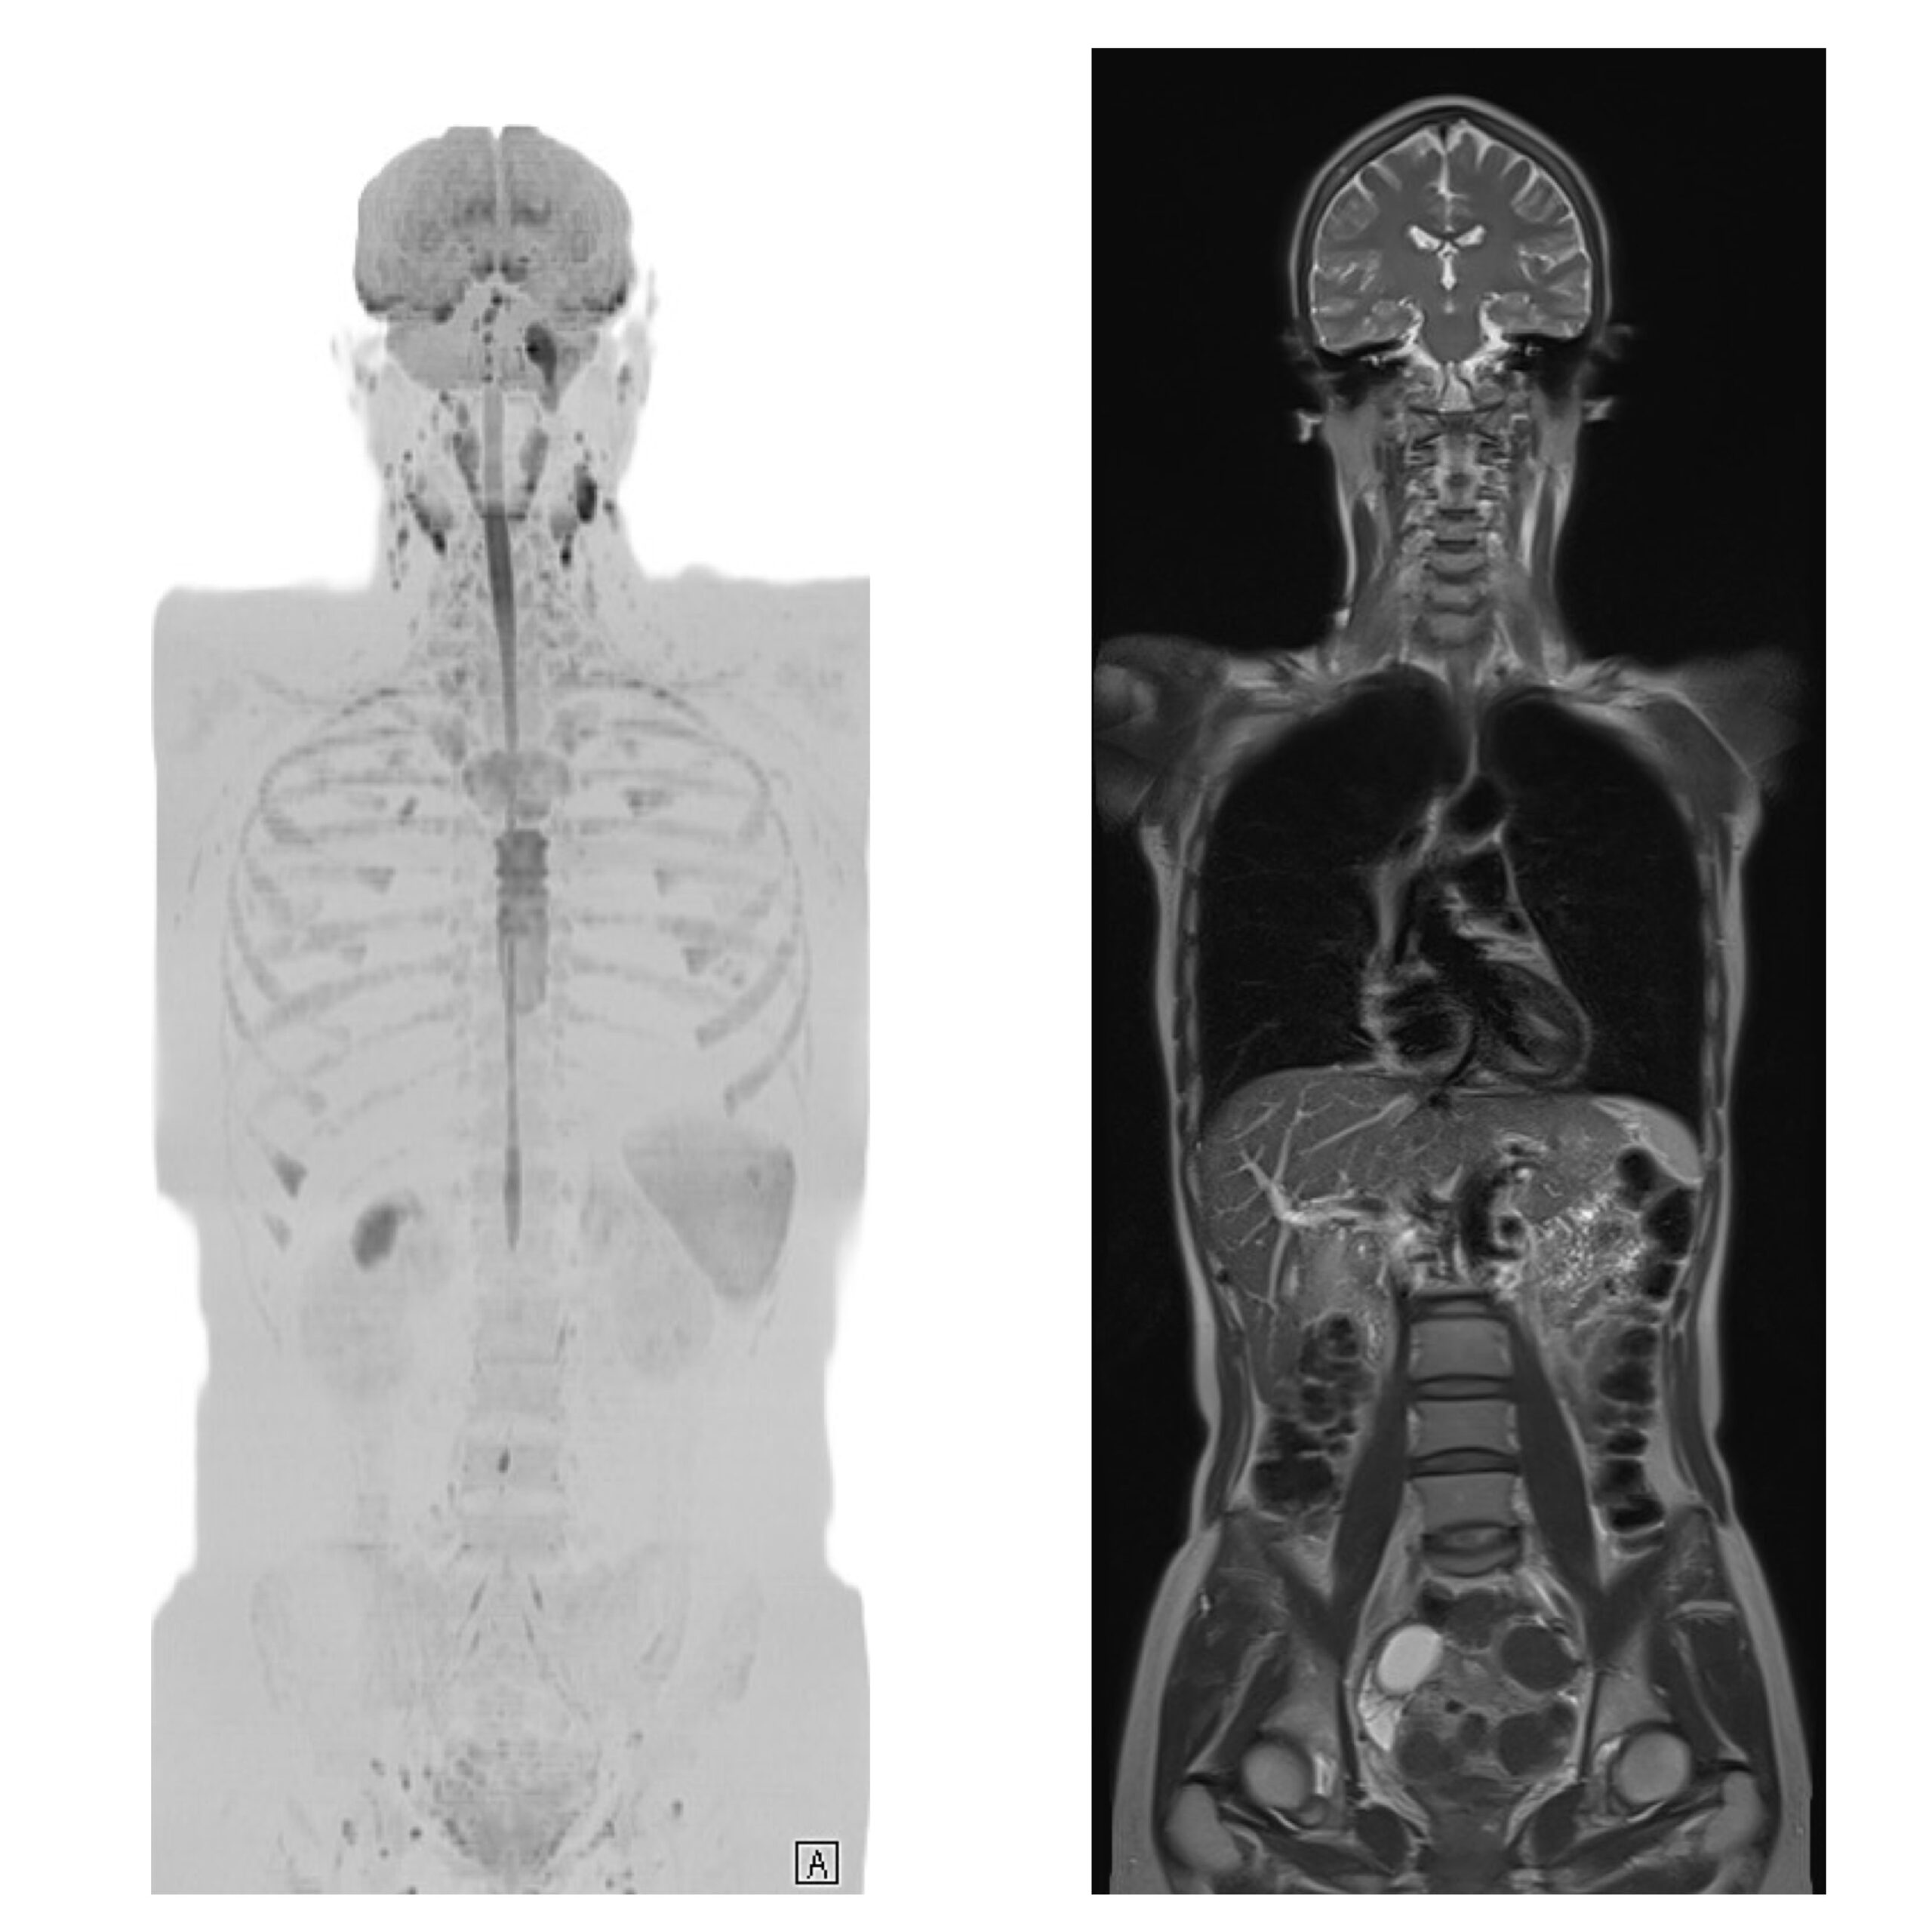

MRI全身がんドック(脳MRI+MRA+躯幹部DWI)

DWIBS法はMRI装置を使ってがんやがんの転移を調べる撮像方法で、PETやPET-CTに代わる新たな全身がん検査です。PET-CTと比較して放射線による被曝がなく、造影剤使用や前処置、食事制限も不要で、1時間以内に撮影終わることがこの検査の特徴です。その上でがんに対する「診断能力に大きな差異はない可能性が高い」とする報告があり、大変注目されています。ただし胃や大腸、肺などの動く臓器は不得意なことに注意し、肺CTや内視鏡検査と組み合わせることでより精度の高いがん検診となります。